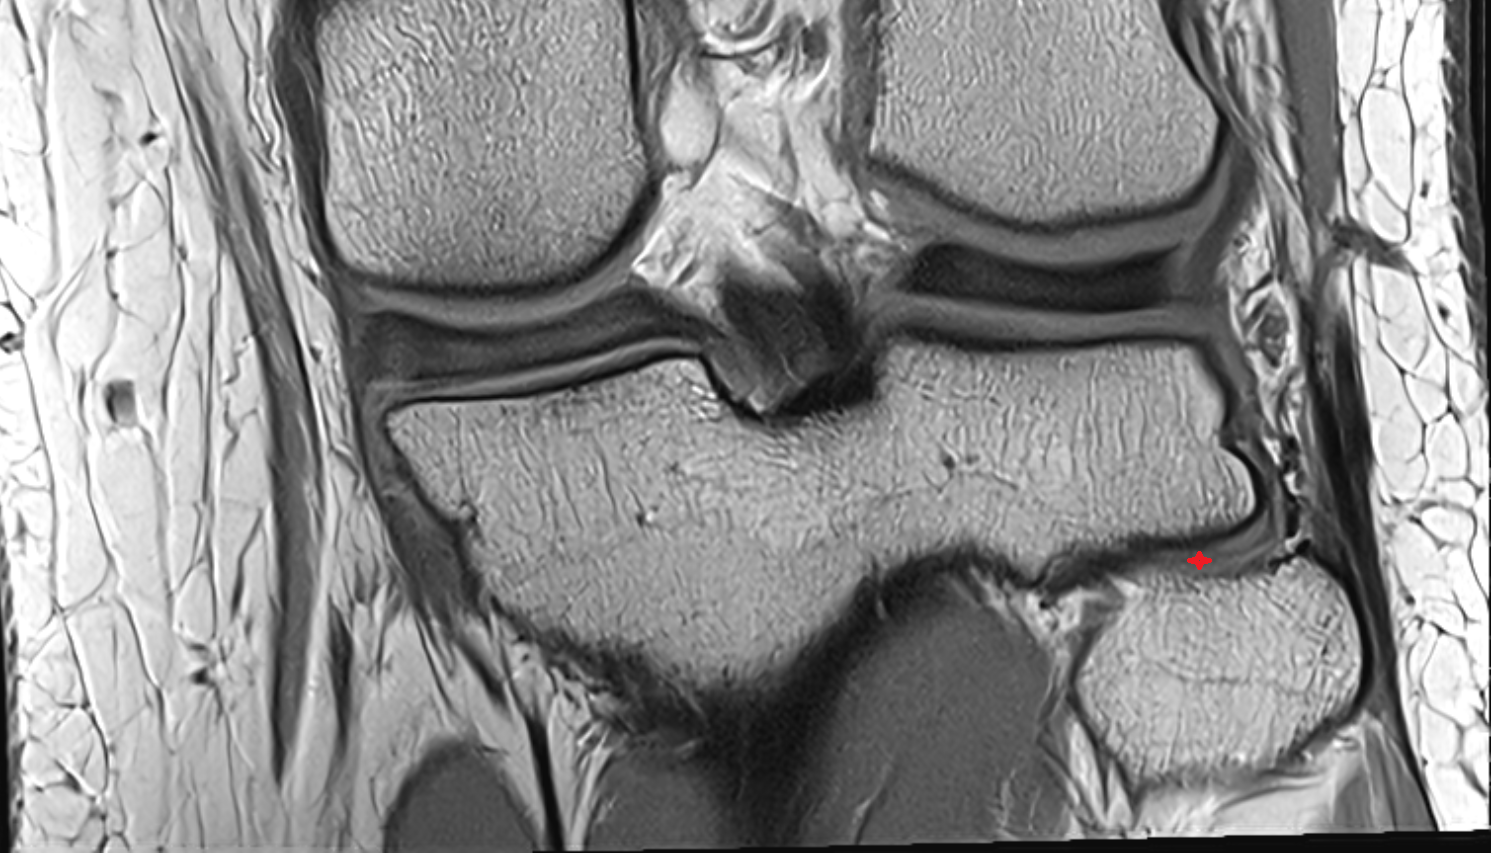

- Medial meniscus

- Lateral meniscus

- Knee Joint